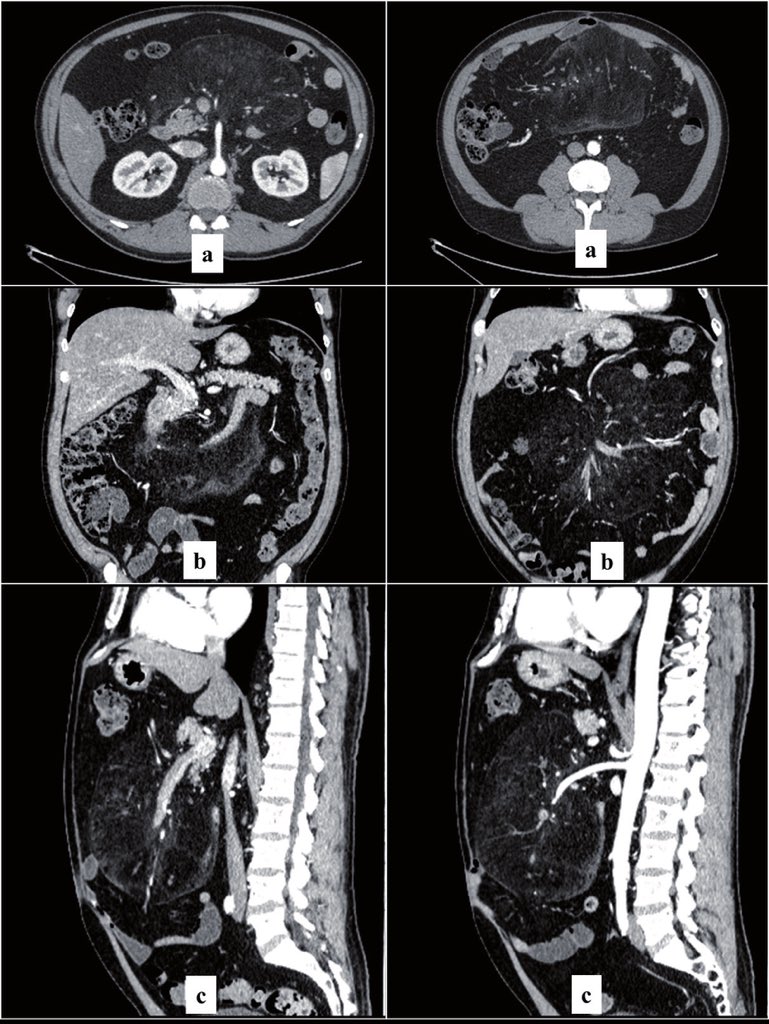

الصبغة المستخدمة في الاشعة تُعطى بأحد الطرق التالية:

← عن طريق الفم (او بعض الأحيان تُحقن في المستقيم): الصورة اليسار

← عن طريق الوريد او الشريان: الصورة اليمين

الصبغة عن طريق الفم او المستقيم تُستخدم لفحص الجهاز الهضمي من البلعوم الى المستقيم ..

للإجابة على السؤال من الافضل تقسيم الاشعة .. نبدأ بالأشعة المقطعية بالصبغة .. والتي بالعادة تُطلب للصدر - البطن - الحوض - الدماغ